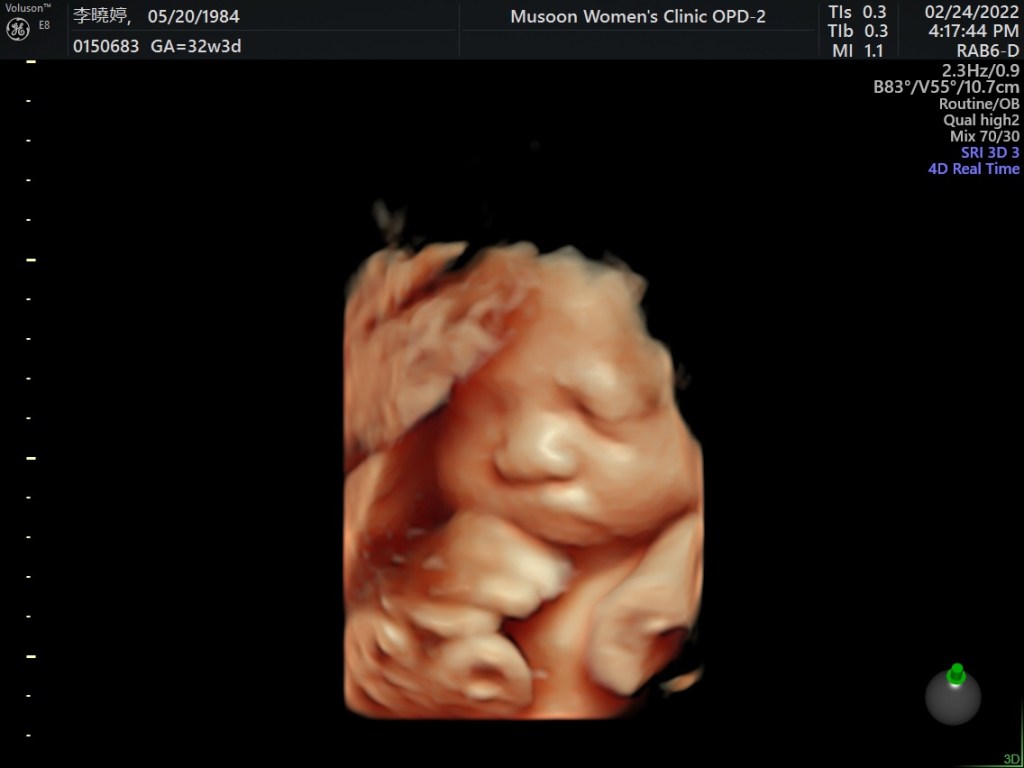

托著9個月大的肚子,行動更是不方便,盆底肌拉扯、骨盆等關節翻身都會出現驚人的“咖一聲”,這輩子還沒聽過恥骨聯合週圍的關節會咖一聲,這也是我唯一痛苦來源。

雖然身體再怎麼不適,但內心感到幸福的,或許知道這是最後一次懷孕,格外珍惜與寶寶同為一體的時間。身為女人擁有懷孕這麼特別的體驗,真的很開心也很幸運的可以體會這件事,感謝我的身體、子宮,還有精神、心靈,短短2年支撐我孕育兩胎的計劃,非常不容易,能撐到同一個時間生產,我都佩服自己了,中間還滑倒劈腿、不斷的顧9公斤的吳藍天而受傷N次,精神上、心靈上承受的壓力,在這疫情期間,每個懷孕的媽媽都承受很大的壓力。